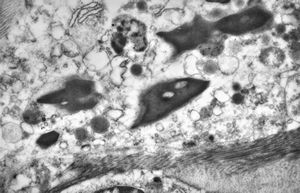

bone marrow - crystalloid inclusions Charcot-Leyden crystals formation

bone marrow - crystalloid inclusions Charcot-Leyden crystals formation v.s.